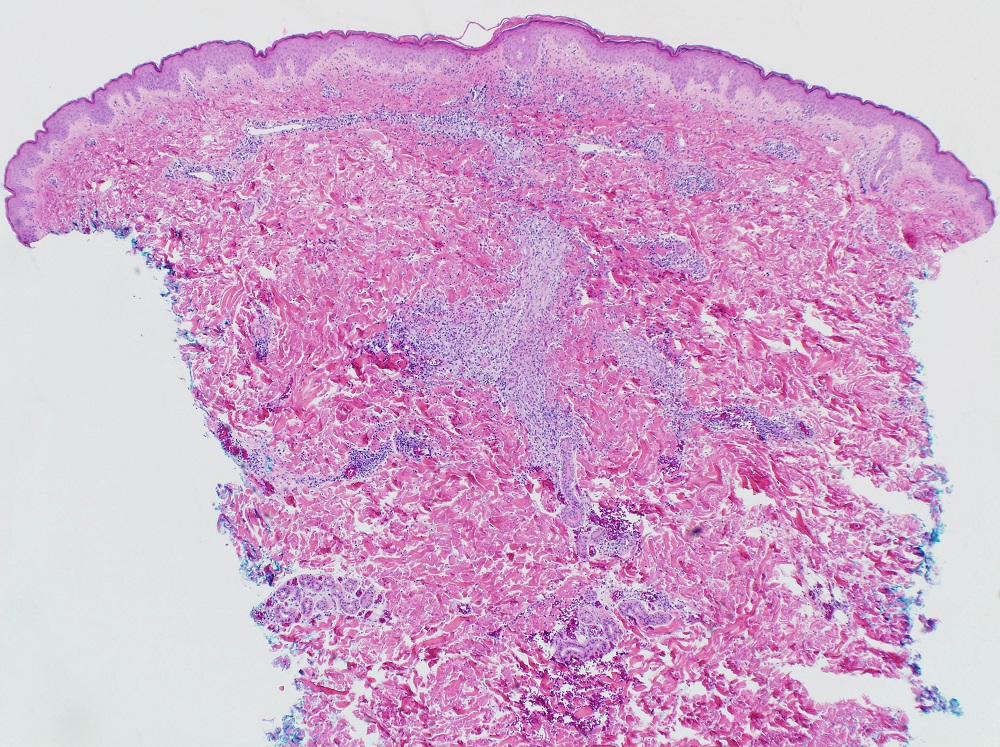

Secções de uma lesão de miliária cristalina coradas com hematoxilina e eosina demonstram uma vesícula subcorneana situada ao longo de um ducto acrossiríngeo sem nenhum infiltrado inflamatório associado.

Secções de uma lesão de miliária profunda coradas com hematoxilina e eosina demonstram uma vesícula espongiótica intraepidérmica associada a um ducto acrossiríngeo com exocitose linfocítica e um infiltrado perivascular superficial de linfócitos e neutrófilos mais denso que o observado na miliária rubra.[Figure caption and citation for the preceding image starts]: Fotomicrografia de miliária cristalina mostrando vesícula subcorneana não inflamatória (H&Ex100)Do acervo de Brian L. Swick, usado com permissão [Citation ends].